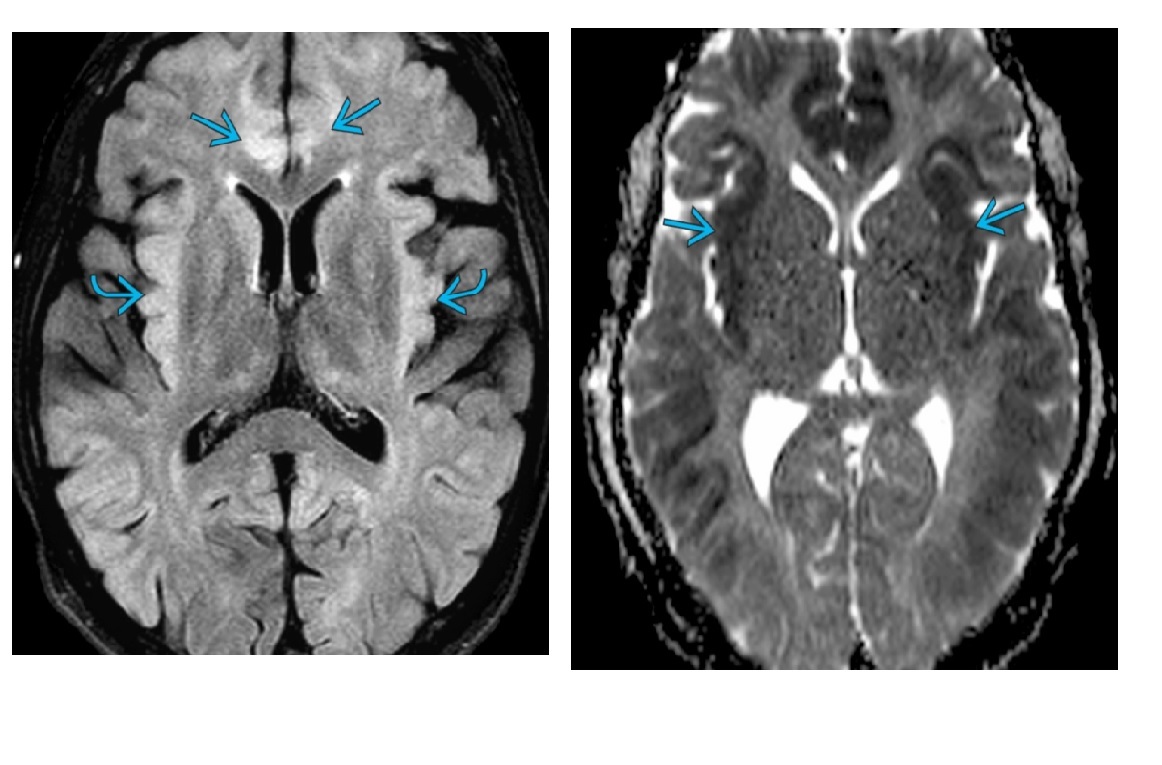

Appearances of acute hepatic encephalopathy?

Bilateral swollen T2-/FLAIR-hyperintense gyri (most severe **insular cortex**, cingulate gyri) with diffusion restriction Remember in Chronic **Bilateral T1 hyperintensity** in globus pallidus (GP)